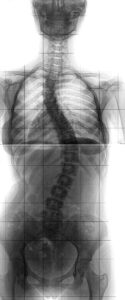

側弯症とピラティス 今日は【側弯症の方に試して欲しいこと】というお話です。 ピラティスのことについての話ですが、代表の高品からお伝えします。 幼少期に「側弯症」の診断を受けている方は意外と多いです。 長年僕が診て(続きを読む)